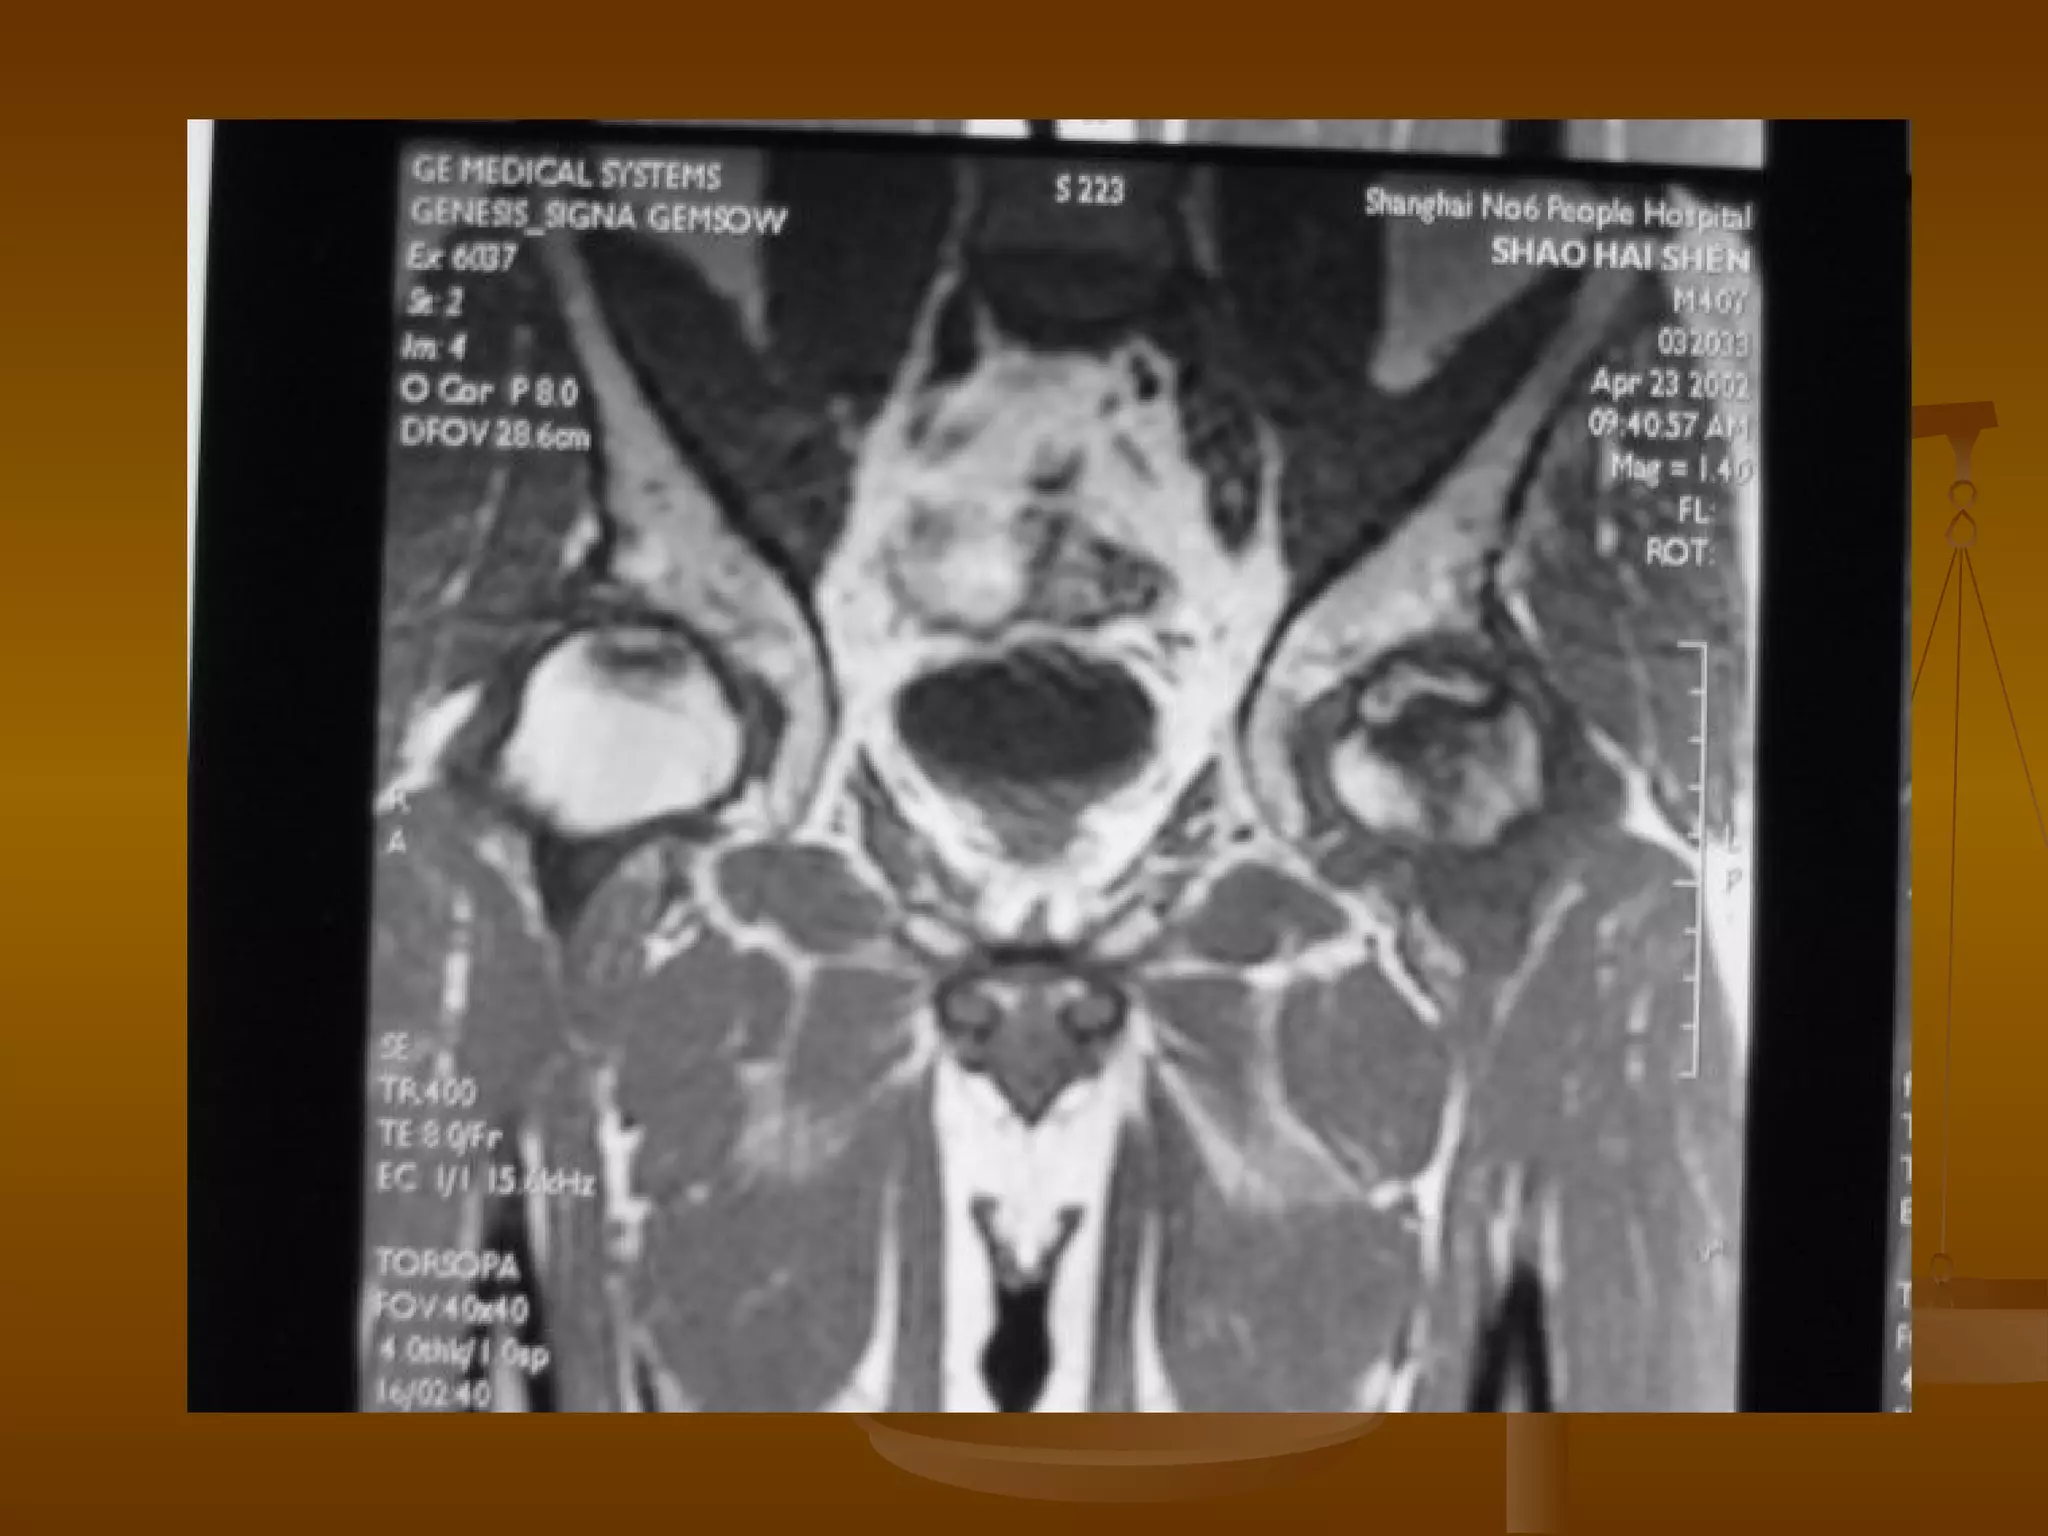

MRI 诊断   MRI 扫描技术 患者取仰卧位,扫描范围自髋臼上 3cm 至股骨粗隆下。 层厚 5mm ,间隔 1mm 连续扫描。 选择自旋回波 SE 序列 T1WI 、 T2WI 及 STIR 冠状面扫描,横轴位 T1W 扫描。

MRI 诊断   Ⅰ 期 髋关节间隙正常,股骨头光整、不变形。 典型的 MRI 表现为股骨头前上部负重区在 T1W 上显示线样低信号区, T2W 上显示为局限性信号升高或“双线征”。 在 MRI 上出现“双线征”,这是股骨头缺血坏死的特异性 MRI 表现之一。

MRI 诊断   Ⅱ期 髋关节间隙正常,股骨头光整、不变形。 在 T1W 上,股骨头前上部负重区,有硬化缘围绕较低、不均匀信号的新月形坏死区。 在 T2W 上,病灶为星月形高信号区。 在 X 线平片上,股骨头负重区内可见高密度的硬化区,内可伴有小囊样改变。